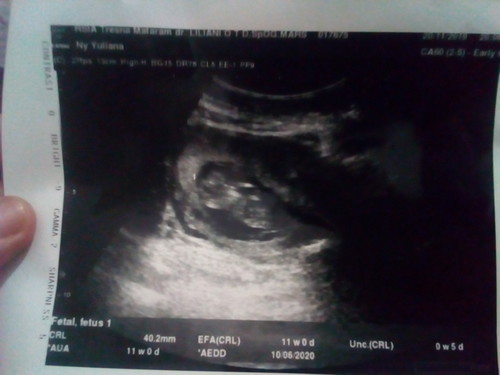

Bentuk kelamin belum kelihatan

Diusia 11w emng belum keliatan bun ๐ Nnt kalau udh 5 jalan 6 bulanan in syaa Allah kalau posisi bayinya bagus bisa keliatan kelamin nya